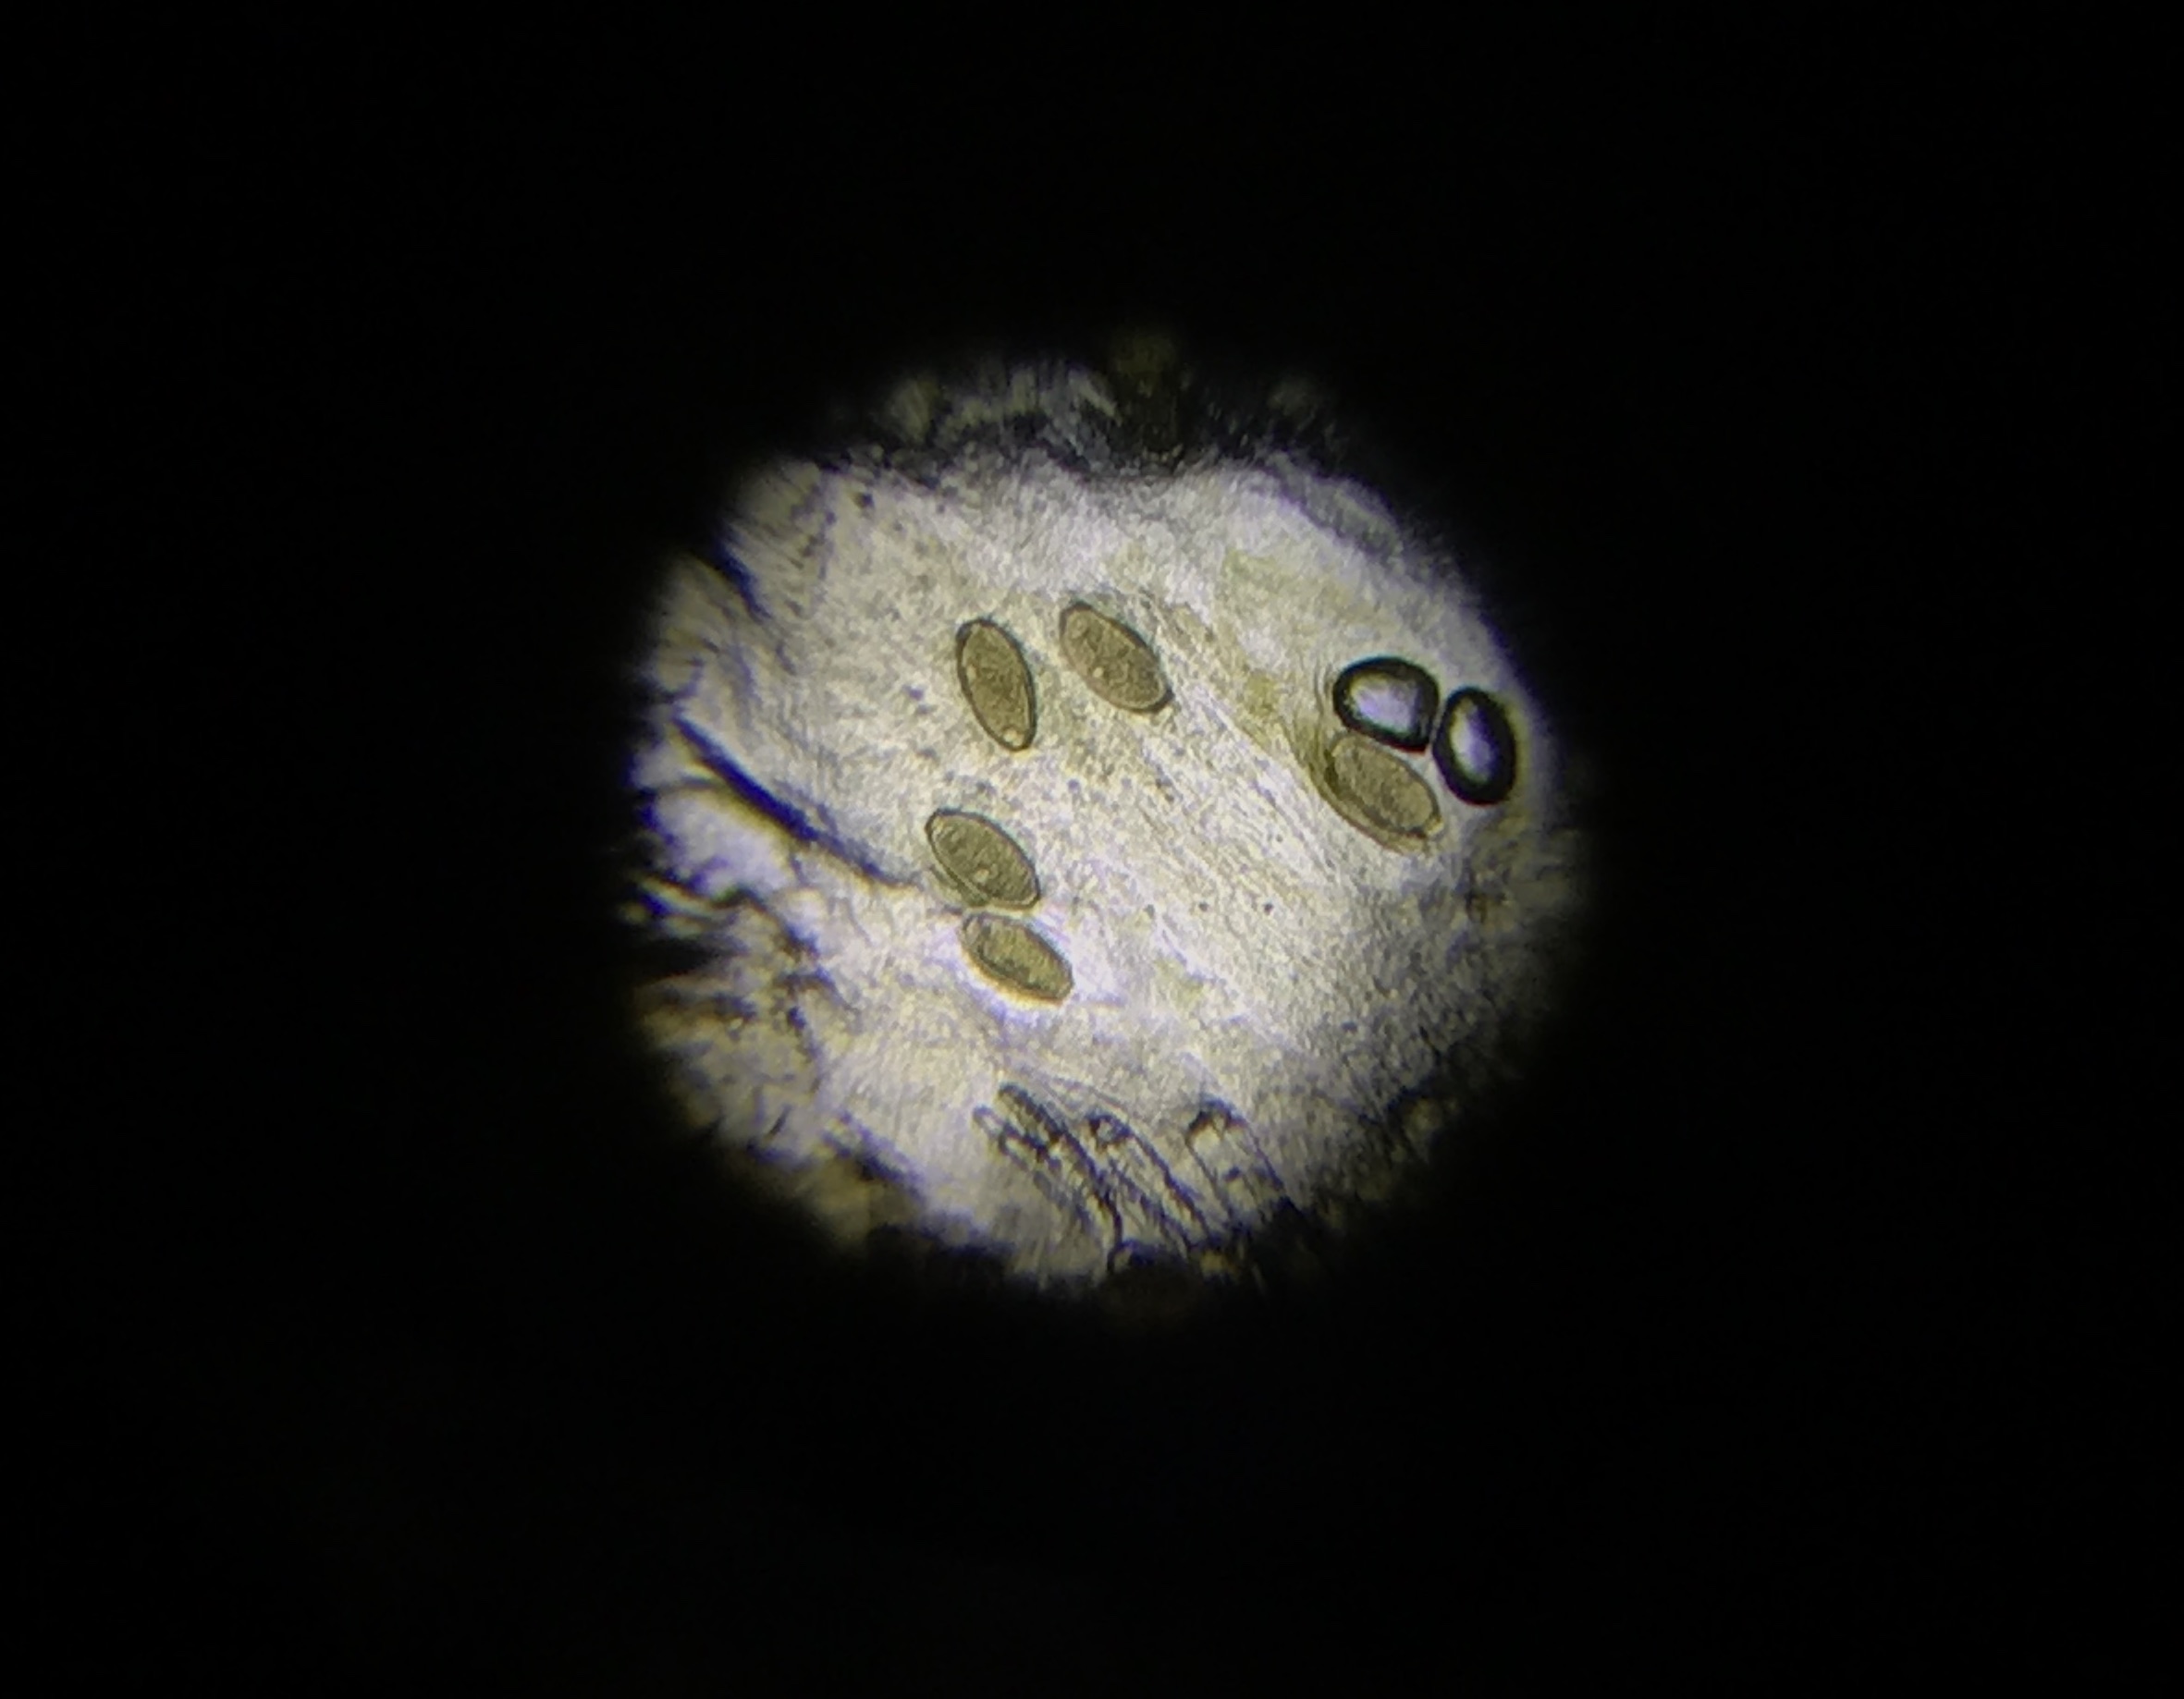

As well as hedgehogs suffering with endoparasites, we are seeing a large number of hedgehogs coming through our doors that have a condition called mange. Mange is caused by mites that burrow into the skin and cause the hedgehog to have crusty lesions on the skin. Hedgehogs often suffer from ringworm simultaneously to mange, and they present with similar symptoms. To diagnose a hedgehog for mange, we can take skin scrapes from them and view these under the microscope. This particular hedgehog in the image was brought into us on Friday 29th January after the finder had seen him on her night vision camera constantly itching. The video shows the mange mites from this hedgehog under the microscope – no wonder he was scratching a lot! He is now on a course of treatment to clear this up and is in isolation as it is highly contagious to other hedgehogs.